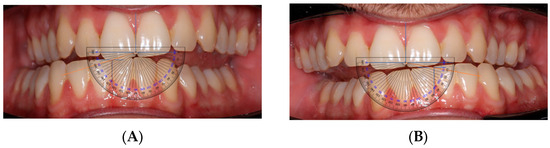

- AFMP Measurement: Horizontal and vertical reference axes were traced on images using PowerPoint. Angles were then measured using a transparent angle protractor overlay (Figure 1). Reference axes were defined using the maxillary incisal edge line and the mandibular interincisal point; vertical axes corresponded to the dental midlines. This procedure was selected as a pragmatic, low-cost alternative to specialized software. It should be regarded as a preliminary clinical tool rather than a standardized protocol.

Figure 1. (A): Right-side AFMP measured using a protractor overlay. (B): Left-side AFMP measured using a protractor overlay. - Radiographic Analysis: A panoramic radiograph was obtained for each participant. A horizontal line was drawn across the hyoid bone, and vertical distances were measured from the upper border of the hyoid to the antegonial notch on each side using a digital ruler overlay (Figure 2). Distances were measured digitally from the most superior point of the hyoid body to the antegonial notch bilaterally, using an on-screen ruler calibrated at the same scale.